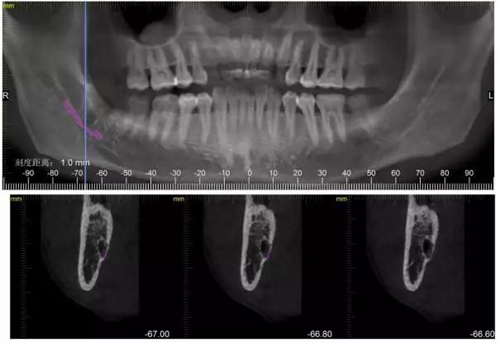

下面CBCT,可以看到兩個(gè)牙根的根尖三分之一在神經(jīng)管里面。

CBCT神經(jīng)管標(biāo)線,可以看到標(biāo)線不能連續(xù),中間被阻斷。

下面拔除后的片子,可以清楚的看到,牙根穿破神經(jīng)管。

1500633362_825152.jpg拔除后。 可以看到神經(jīng)管皮質(zhì)骨的不連續(xù)。